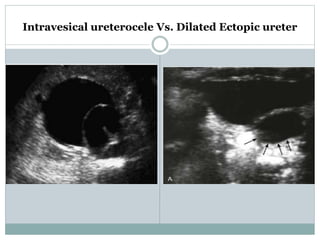

ULTRASOUND:

 Bladder images differentiate ureterocele from ectopic

ureter- thin-walled cystic dilation within the bladder,

Intravesical ureterocele Vs. Dilated Ectopic ureter